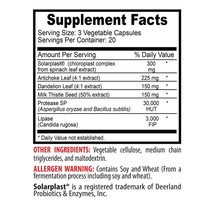

SUPPLEMENT FACTS

Amount Per Serving

Serving Size: 2 Capsules

* Daily Value not established.

Servings Per Container: 50 Supplement Facts

% Daily Value

1000 mg * Beef Liver (Argentine)

100 mg * Milk Thistle (Silybum marianum) (seed) (standardized to contain 80% silymarin)

100 mg * Siberian Ginseng (Eleutherococcus senticosus) (root)

OTHER INGREDIENTS: Rice Powder, Gelatin Capsule, Vegetable Magnesium Stearate, Silica.